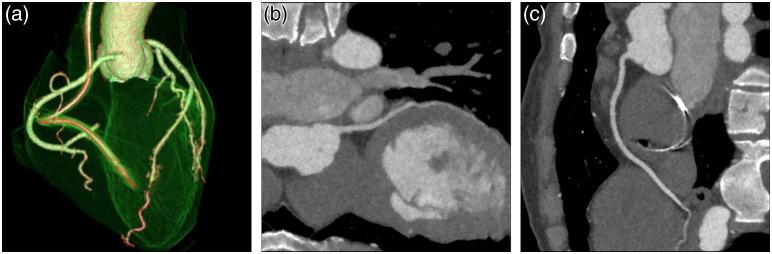

We provide a review of the key computed tomography (CT) technologies developed since the late 1980s and offer an overview of one of the future technologies under development. The focus of this review is mainly on the hardware and system development. The topics on the historical event linked to the early days of CT development and other innovations that contributed to the CT development, such as advanced image reconstruction techniques, are covered by companion papers in this special issue. The review is divided into five major sections, each linked to a key innovation in CT: helical spiral data acquisition, multi-slice CT, wide-cone CT, dual-source CT, and spectral CT. Given the limited scope of this review, only one of the future technologies, photon-counting CT, is discussed in detail. Whenever possible, both theory of operation and clinical examples are provided. Theoretical analyses, phantom results, and clinical examples clearly demonstrate the efficacy and clinical relevancy of five historical technology developments and one future technology in CT. These technologies have improved and will continue to improve CT performance in terms of isotropic volume coverage, improved temporal resolution, and material differentiation and characterization capabilities. Over the past 30 years, technological developments of CT have contributed to the success of CT in many clinical applications such as trauma, oncology, cardiac imaging, and stroke. Advanced clinical applications have and will continue to demand more advanced technology development.

我们回顾了自20世纪80年代末以来开发的关键计算机断层扫描(CT)技术,并概述了一种正在开发的未来技术。本综述的重点主要是硬件和系统开发。与CT早期发展相关的历史事件以及其他有助于CT发展的创新,如先进的图像重建技术等主题,在本期特刊的相关论文中有所涵盖。本综述分为五个主要部分,每个部分都与CT的一项关键创新相关:螺旋数据采集、多层CT、宽锥CT、双源CT和光谱CT。鉴于本综述的范围有限,仅详细讨论了一种未来技术——光子计数CT。只要有可能,都会提供操作原理和临床实例。理论分析、模型结果和临床实例清楚地证明了CT的五项历史技术发展和一项未来技术的有效性和临床相关性。这些技术已经并将继续在各向同性容积覆盖、提高时间分辨率以及物质区分和表征能力方面改善CT性能。在过去30年里,CT的技术发展推动了CT在创伤、肿瘤学、心脏成像和中风等许多临床应用中的成功。先进的临床应用已经并将继续需要更先进的技术发展。